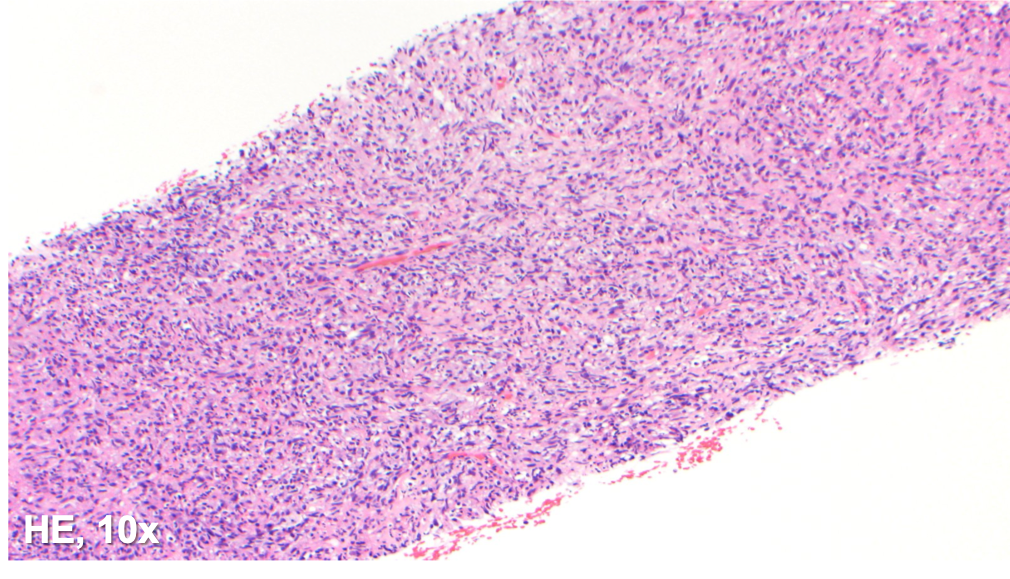

The specimen shows a tissue core with a diffuse histiocytic proliferation and scattered plasma cells. No lymph node architecture is identified. Many of the cells are plump and with abundant foamy cytoplasm, while others appear spindled in morphology.

In a young patient with a history of HIV and prior sepsis, an infectious lymphadenitis should be considered highly in the differential diagnosis. Bacterial lymphadenitis caused by Mycobacterium tuberculosis is generally characterized by necrotizing granulomatous inflammation, with the bacilli localized within the necrotic area. Atypical mycobacterial lymphadenitis is the result of nontuberculous mycobacteria, and nearly 80% are caused by Mycobacterium avium-intracellulare complex (MAC). The main histologic finding includes the coexistence of necrotizing and nonnecrotizing granulomatous inflammation with abundant bacterial organisms within the foamy macrophages. Additionally, a mycobacterial spindle cell psuedotumor can present as granulomatous inflammation in response to the infection by mycobacterial organisms; the histiocytes exhibit a spindle cell morphology, forming fascicles with or without whorling.